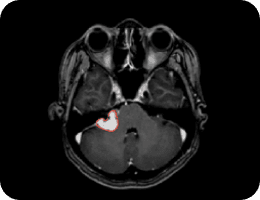

TSHA Project (FEMH)

Meningioma

Neuroma

Stroke Project (CGMH-Kaohsiung)

NCCT Stroke Region